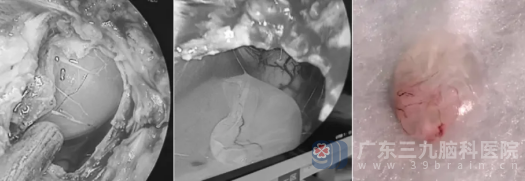

征得患儿家属同意后,7月11日,神经外十科手术团队在全麻下选择枕下正中切口入路,沿项白线切开显露枕骨大孔及颈1椎体,逐层切开寰枕筋膜与硬膜,进入到小脑延髓池。

在内镜的清晰视野下,医生们清晰地看到延髓颈髓交界区背侧、颈1椎管内的囊状占位,幸运的是,该占位与延髓颈髓无明显粘连,只是边缘可见数个小血管。手术团队沉着冷静,精准分离,成功取出囊状占位及所有囊膜。手术过程顺利。

术中及切除的肿瘤(右1)